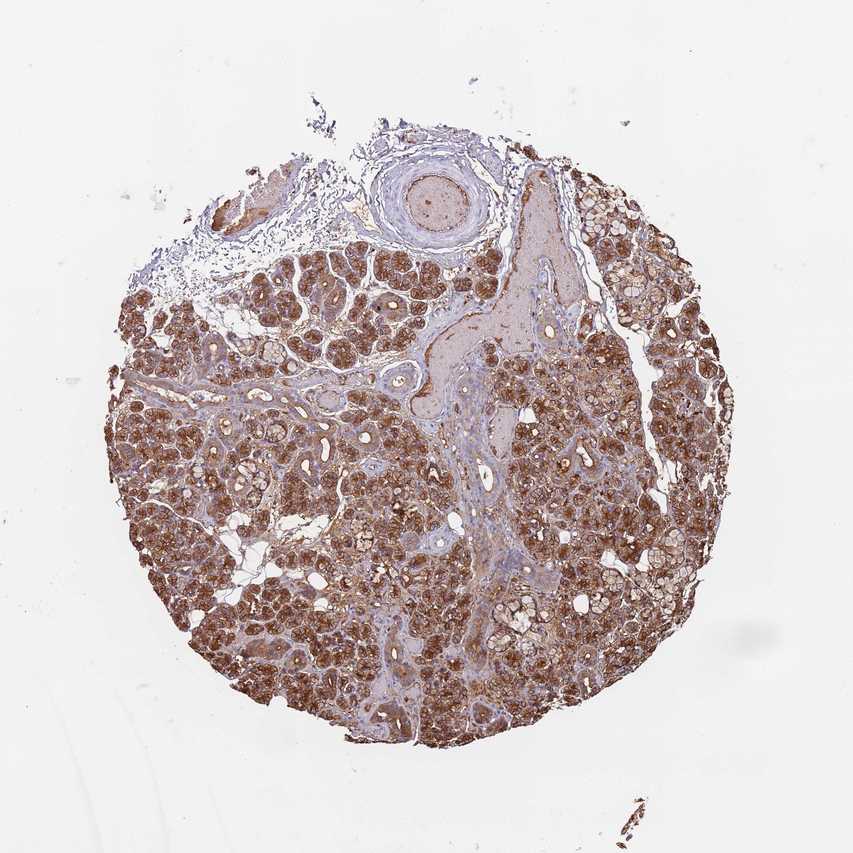

SALIVARY GLAND - Antibody stainingi

Antibody staining in the annotated cell types in the current human tissue is reported as not detected, low, medium, or high, based on conventional immunohistochemistry profiling in selected tissues. This score is based on the combination of the staining intensity and fraction of stained cells.

Each image is clickable and will lead to virtual microscopy that enables deeper exploration of all samples and also displays staining intensity scores, fraction scores and subcellular localization as well as patient and tissue information for each sample.

Antibody HPA046528

Glandular cells High